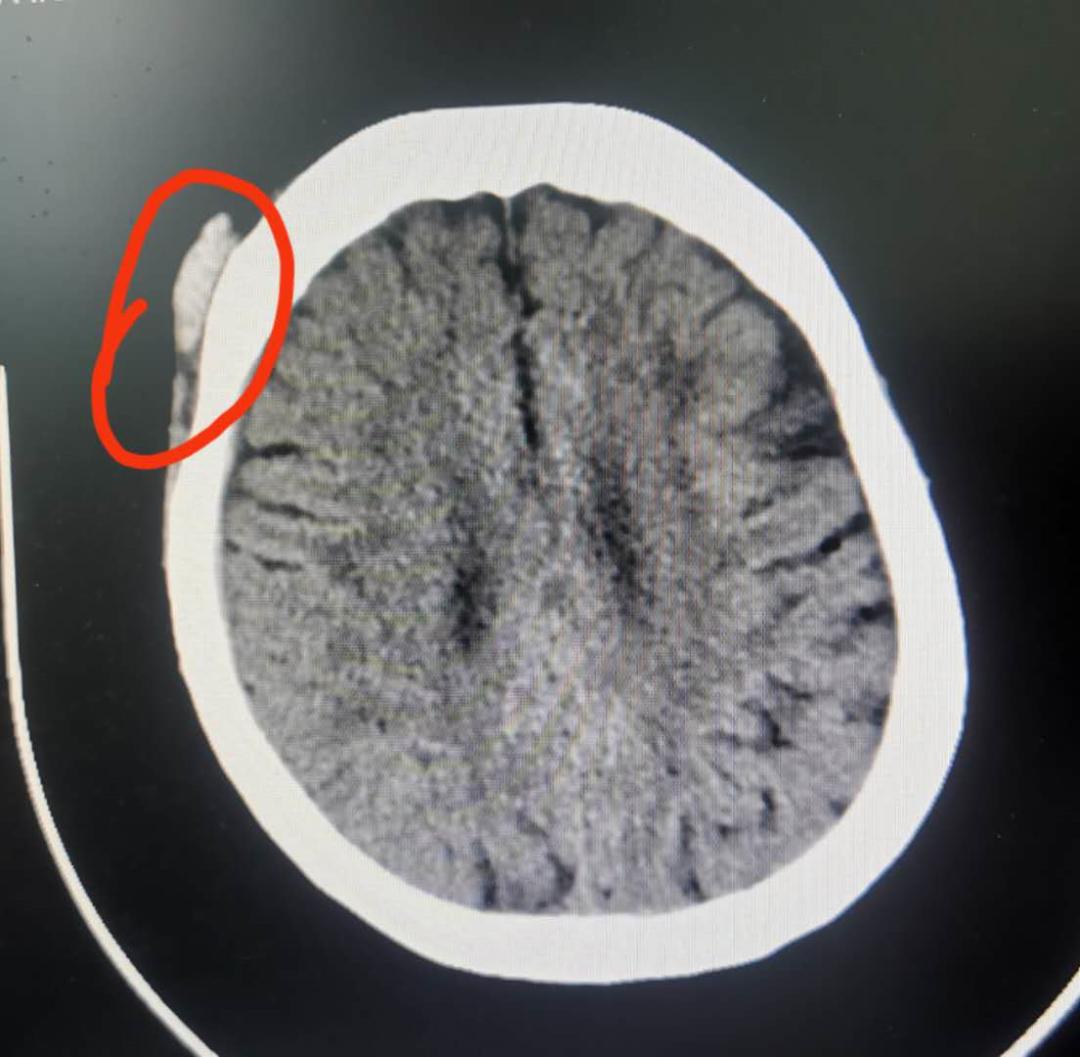

于是安排她做了CT排除颅内出血

检查结果发现王奶奶有皮下软组织肿胀

颅内未出血